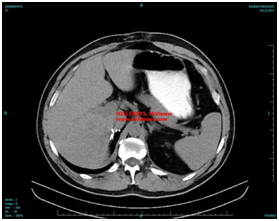

A localized specific adrenal CT scan revealed a hypodense, clear delimited mass of the right adrenal gland, with dimensions of 8x4x6,6 cm, without contrast enhancement, measured of 11 Housefield units., mainly characterized by the radiologist as adenoma see Figure 1.

Figure 1 Radiologic Findings A localized specific adrenal CT scan.